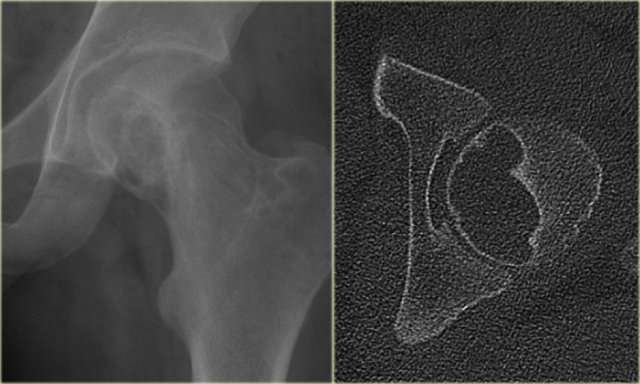

Chondroblastoma (5)

On the left an eccentric well-defined lytic lesion in the proximal femur.

CT image shows a lobulated and sclerotic border.

The location in the epiphysis is typical for a chondroblastoma.

Continue with the MR.

Same patient.

Coronal T2-WI with FS demonstrates high SI of the lesion with a low intensity sclerotic border with perilesional edema.